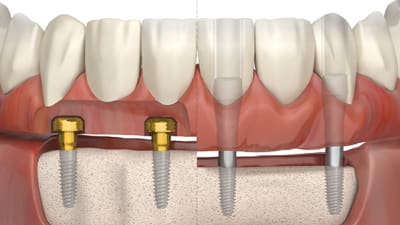

Case Series Implantology Implant Placement Lateral to the Inferior Alveolar Nerve: Selective Indications and Treatment Outcomes—A Case Series By Georges Tawil, DDS, Peter Tawil, DDSDDS, Ziad Salameh, DDS September 01, 2022 21 min read

Special Report Implantology Simplicity Is the Key to Zest Dental’s New LOCATOR FIXED™ System September 01, 2022 3 min read